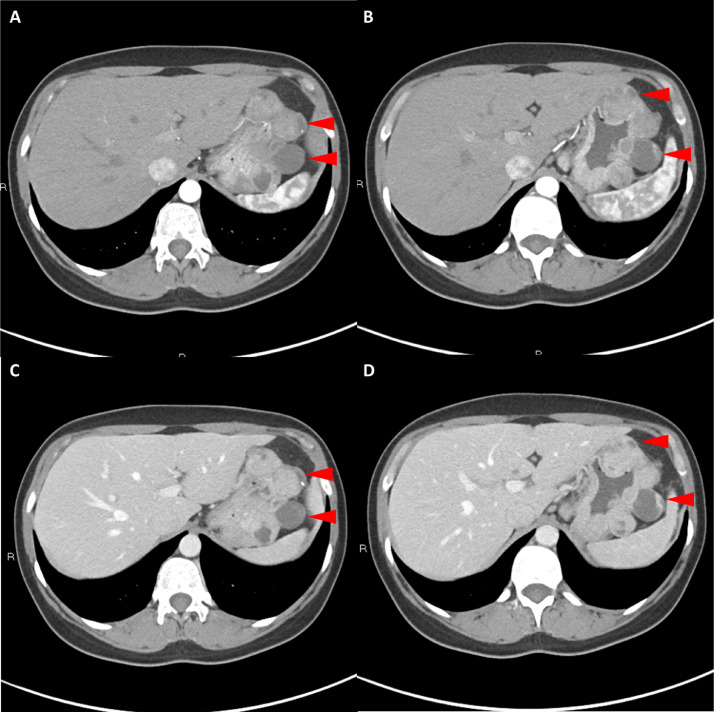

胸部、腹部和骨盆的对比增强动脉和静脉期 CT 显示多个圆形、主要是血管丰富的异质肿块,具有囊性和实性成分,起源于胃底和胃体(图 2-4)。 病变部分呈外生结构,被认为位于粘膜下层。 在颈部多发同步性副神经节瘤的情况下,最初的鉴别诊断包括多发性副神经节瘤、多发性 GIST 以及转移性疾病。